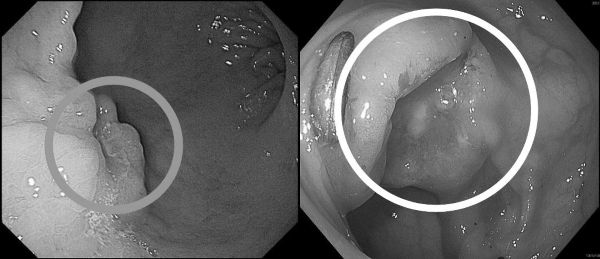

收治病人的高醫岡山醫院一般及消化系外科主任吳柏宣表示,張先生因突發上腹悶痛、糞便顏色變黑,由家人陪同到急診就醫。因懷疑有消化道出血,安排胃鏡檢查,在胃部發現兩公分惡性腫瘤,進一步做大腸鏡檢查,確認乙狀結腸也有一處3公分腫瘤,所幸兩處皆為可手術根治之病灶。

圖說二:病人接受詳細檢查,醫師在其胃部及乙狀結腸內均發現癌灶(圓圈處)。圖/高醫岡山醫院提供